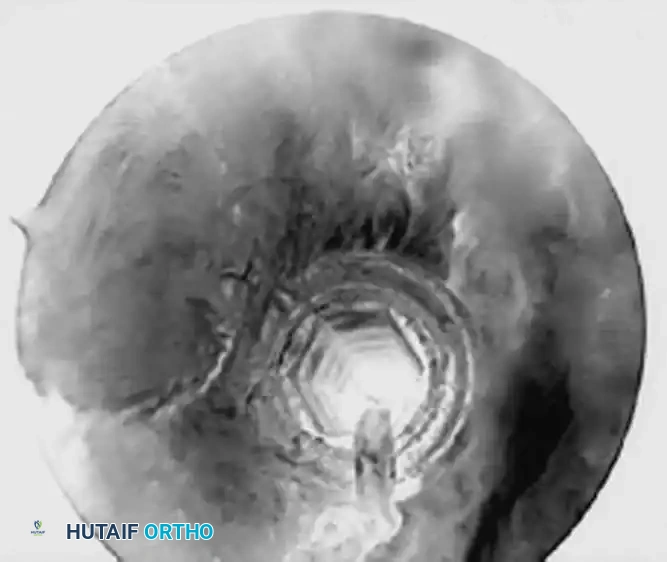

Routine diagnostic arthroscopy is performed using a 4-mm, 30-degree oblique arthroscope. This angle allows for comprehensive visualization of the entire joint through rotation of the lens and manipulation of the arm. In complex instability cases, switching to a 70-degree arthroscope dramatically improves visualization of the anterior glenoid neck and the inferior glenohumeral ligament, which is critical during arthroscopic capsulorrhaphy.